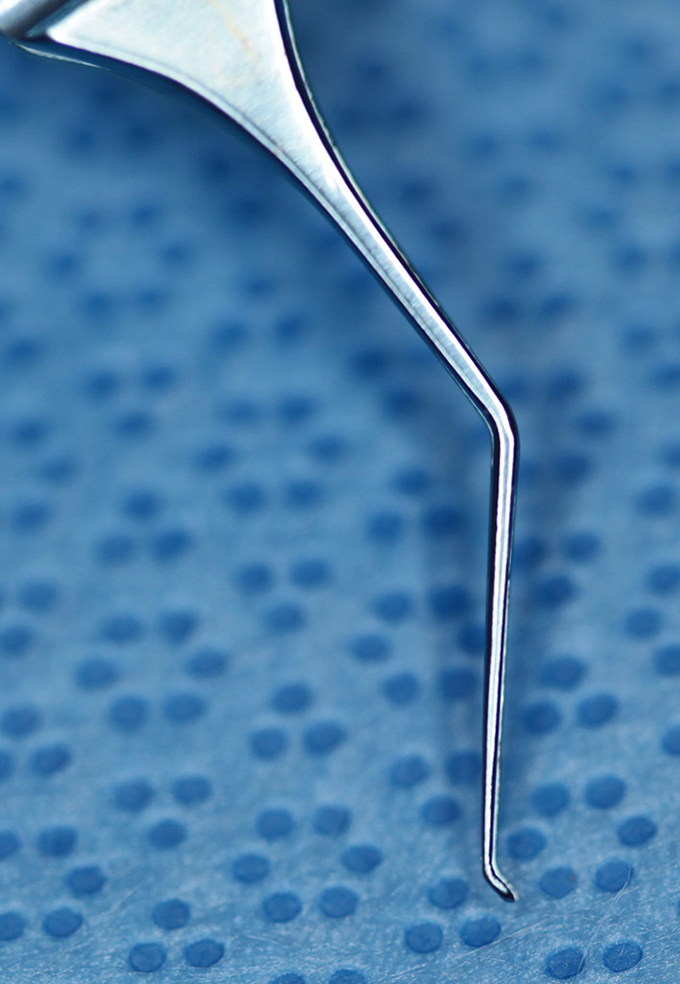

Forcep Thumb, Utrata (Enlarged)

(aka Utrara Forceps)

catalog number: Storz 2-719

Typical Use(s): Capsulorhexis; Remove stuck haptic from IOL optic